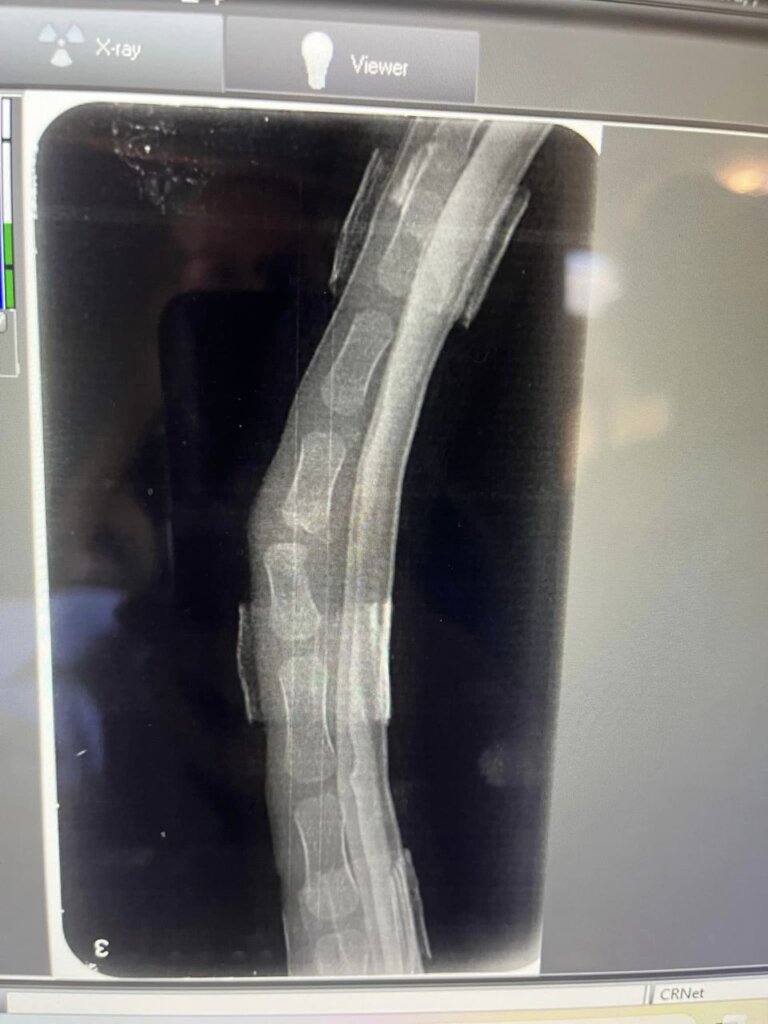

Little Curly was taken to Mona Vale Veterinary Hospital for radiographs and examined. It appeared that the tail deformity was a result of a congenital birth defect, rather than trauma-induced! But it still needed to be corrected.

Little Curly was referred to Sydney Wildlife's Mobile Care Unit and he has become quite the regular! Dr Reiner and Dr Bryn undertook the procedure to realign his tail so that he would be able to use it as nature intended.

The procedure was tricky as the alignment needed to be achieved without affecting nerves, ligaments and tendons. The tail was splinted to ensure that it stays in alignment as he grows.